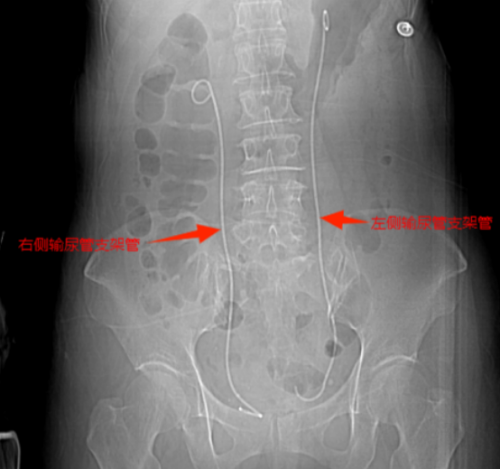

双侧输尿管支架置入后解除尿路梗阻